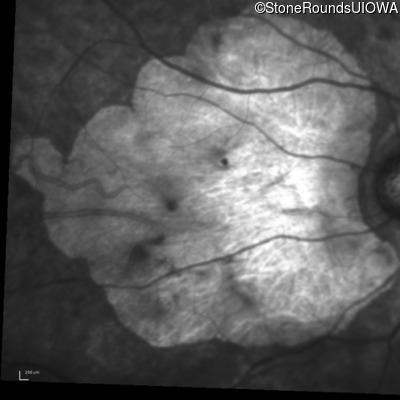

Infrared Fundus Photograph - Right - 20/300

Exemplar

Infrared Fundus Photograph - Left - 20/500